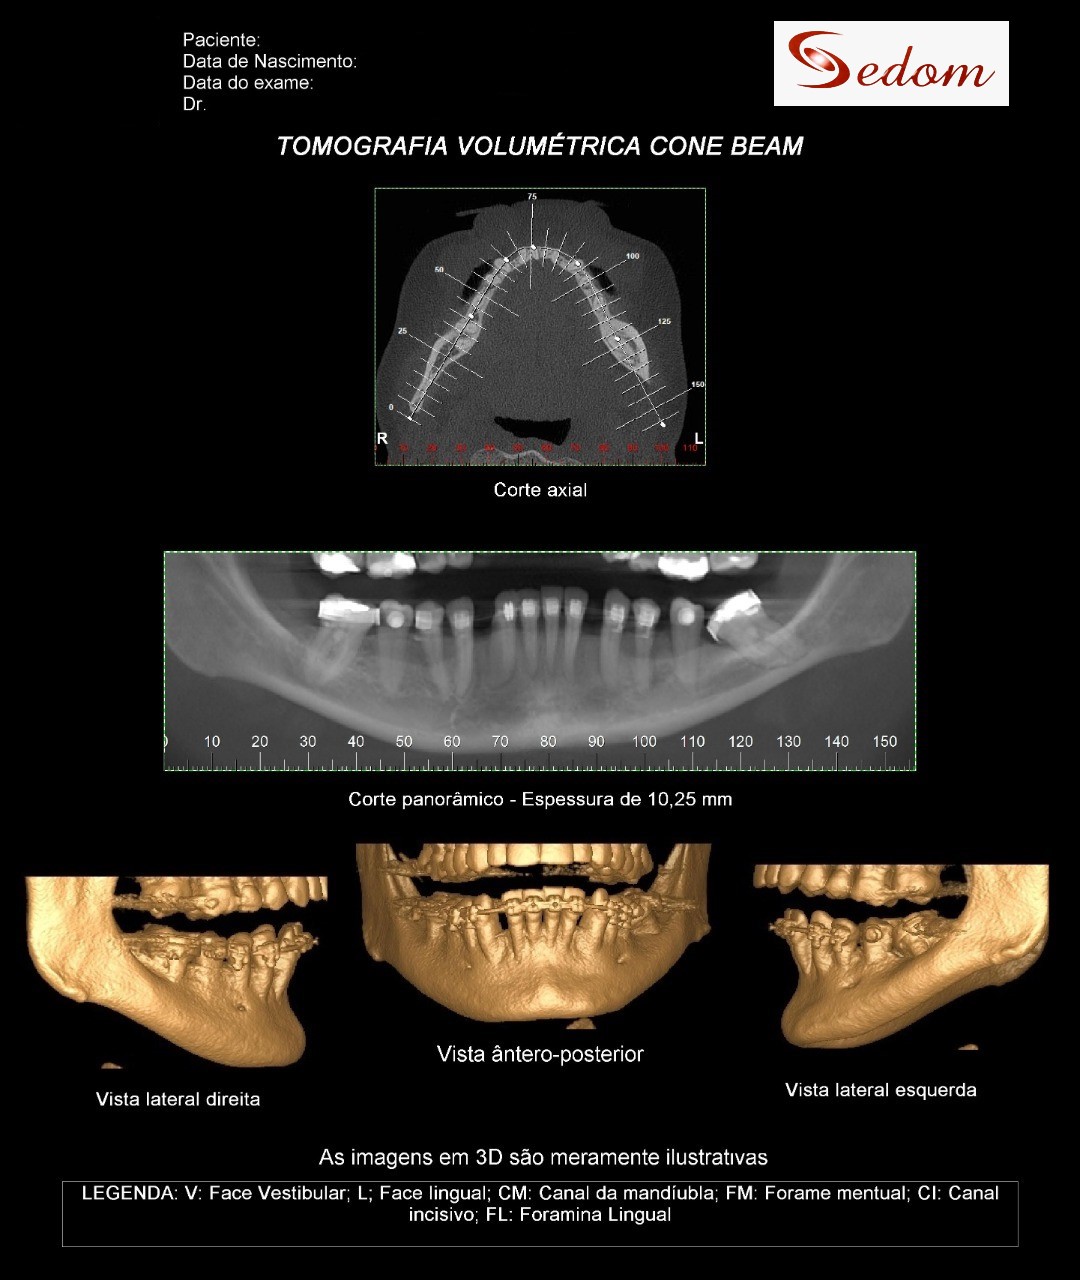

Tomografia Computadorizada

Exame Tridimensional dos maxilares

Tomografia para endodontia

Implantodontia e demais áreas odontológicas